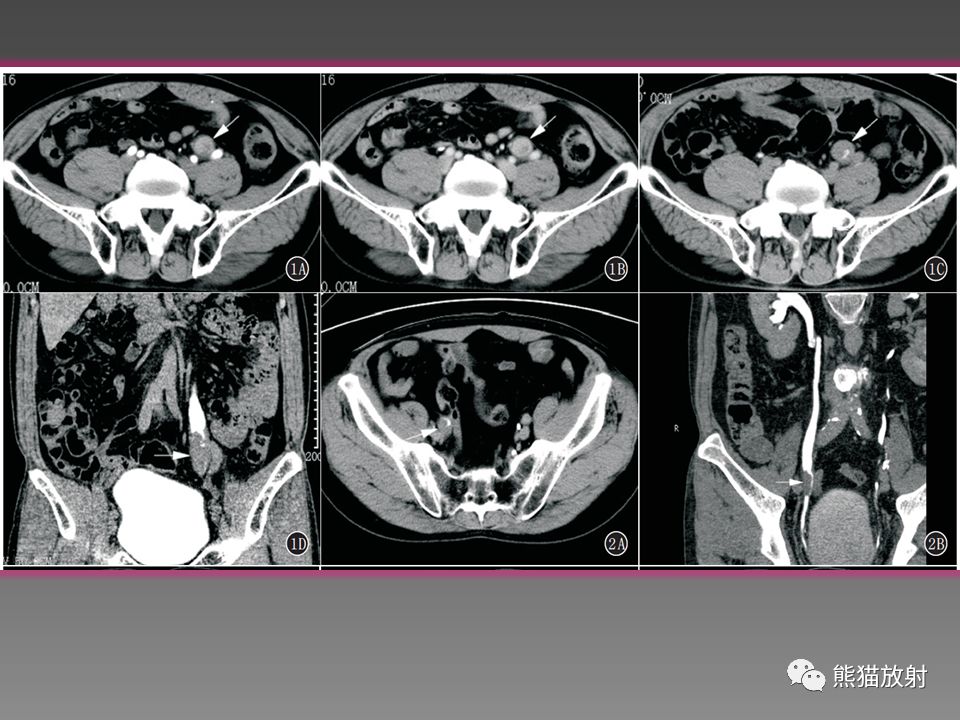

输尿管肿瘤影像诊断及鉴别诊断

图片尺寸960x720